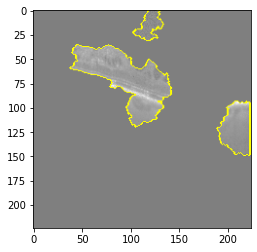

Original Image

Explanation B

Explanation C

Explanation D

GradCAM

Original Image

Explanation B

Explanation C

Explanation D

GradCAM

Original Image

Explanation B

Explanation C

Explanation D

GradCAM

Fig 6, 7, 8 and 9 depicts the visualization of correct predictions by our proposed CNN model where fig 6 is class CNV, fig 8 is class DME, fig 7 is DRUSEN and finally, fig 9 is NORMAL. Here the first photo in every class is the original image. The LIME map of our suggested model’s prediction is shown in image B whereas in image C the positive region is highlighted in specific sections on the original image. For Image D we have increased the number of features from 5 to 10 thus more regions have been predicted as the positive region which is highlighted in green. After increasing the features from 5 to 10, some of the regions are predicted wrongly. The red regions represent the output of incorrect prediction. The following image represents the Grad-CAM heatmap highlighting the regions with our model’s prediction.